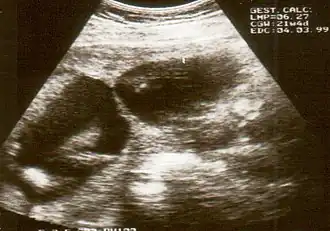

![]() Визуализация перетяжки при ультразвуковом обследовании | |

Амниотические перетяжки не всегда обнаруживаются при УЗИ, так как они очень тонкие. Иногда их наличие устанавливают косвенно по набухшим/увеличенным из-за вдавлений конечностям. Распространена и гипердиагностика. Поэтому, если появляется предположение, что обнаружены амниотические тяжи, показаны дальнейшие исследования (3D УЗИ, МРТ, эхокардиограмма эмбриона) для определения серьезности ситуации.